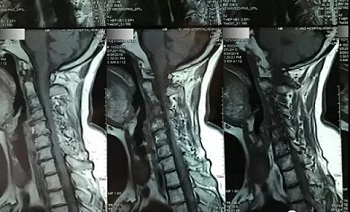

(区域1)

(区域2)

(区域3)

(区域4)

(区域5)

(区域6)

(区域7)

(区域8)